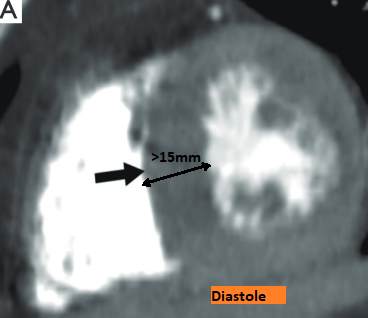

- Cutoff: Septum du VG > 15mm en diastole (13 mm si anamnèse familiale positive)

Cardiomyopathie Hypertrophique

- Hypertrophie concentrique